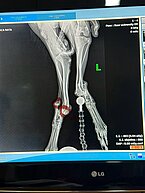

Sonstige Infos: super verschmust, alter Bruch am Hinterlauf, Stummelschwanz

Manchmal muss die Zeit erst reif sein für etwas Neues ... BROWNIE lebte mind. 2,5 Jahre wild im Campo und wollte sich nicht fangen lassen. Wir wissen das so genau, weil wir ihn in dieser Zeit oft selbst gesehen und versucht haben ihn zu fangen. Vor ein paar Wochen trafen wir ihn wieder - und es war, als wollte er sagen "ich bin dann jetzt so weit". Er ist einfach mit uns gegangen und seither der pflegeleichteste Schatz der Welt.

BROWNIE schätzen wir auf ca. 5 Jahre, er ist ca. 55 cm hoch und ein sehr souveräner, verträglicher und menschenfreundlicher Hund, der trotz seiner Vergangenheit wahnsinnig gern kuschelt. Wir meinen ein bisschen Bretone in ihm zu entdecken, zumal der Stummelschwanz darauf hinweist.

BROWNIE hatte vor einigen Monaten einen Unfall und verletzte sich schwer am Sprunggelenk - auch das konnten wir beobachten. Zum Glück verheilte das Bein auch ohne tierärztliche Unterstützung, sodass er heute ganz normal läuft; nur eine Verdickung am Gelenk deutet noch auf den Unfall hin. Wir werden das aber noch genau abklären.

Sonstige Infos: beidseitig luxierte Sprunggelenke

NATA wurde am 5.November 24 erfolgreich an einem Bein operiert und braucht nun einige Wochen Ruhe.

Danach wird das zweite Bein operiert.